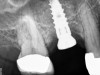

The implant is then delivered and should be well stabilized in the bone. If there is any mobility of the implant, it can either be placed a little deeper (if there is enough native bone) or the implant can be removed and the procedure aborted, in which case it would be a two-stage procedure. This should rarely occur with the tapered designed implant, even with only 2 mm of native bone. Using a bone-level platform-shifting implant (or a tissue-level designed implant) is critical, as the hard and soft tissue will establish a biologic width. If an external hex type of implant is used and the shoulder is placed at the bone level, an expected bone loss of 1.5 mm to 2 mm will occur.24 Figure 10 shows proper bone-level implant depth placement with a platform-shifting design. In this case, a 3-mm healing abutment was placed at the time of surgery to avoid a secondary uncovering surgery, but an implant-level healing abutment could have been placed instead. As can be seen, there was only about 2 mm to 3 mm of native bone height. The membrane was raised about 8 mm to 9 mm. Comparing the radiograph on the day of surgery (Figure 10) to the 6-month postoperative radiograph (Figure 11) shows no loss of native bone, as well as the positive change in appearance of the grafted bone. The 3.5-month CBCT scan (Figure 12) shows good healing of the bone with no coronal bone loss. With minimal native bone present, as in this case, the use of a non-platform-shifting or non-tissue-level implant design could be problematic. After 1.5 mm to 2 mm of crestal bone loss, an external hex designed implant could develop instability with possible implant failure. If a non-tapered implant is used and bone loss occurs during healing, migration of the implant into the sinus could potentially occur. The surgeon can use either a healing abutment or implant-level closure screw over the implant shoulder. With patients who tend to use their tongues to explore or play with the area, or if the area is under a removable partial denture, a closure screw is recommended.

A 74-year-old man presented with only about 2 mm to 3 mm of native bone below the sinus in the No. 14 position (Figure 13). The composite graft used was an approximately 50:50 mixture of DFDBA (Bio-Oss®, Geistlich Biomaterials, www.bio-oss.com) with the addition of about 40% calcium sulfate by volume (Figure 14). The implant placed (Figure 15) was a 10-mm long, rough-surfaced, platform-shifting implant (tapered 4.2 mm to 2.8 mm), and the sinus was raised about 8 mm. The postoperative radiograph taken at 4 months (Figure 16) showed some shrinkage of the graft, but no demarcation of the old sinus floor in the area.